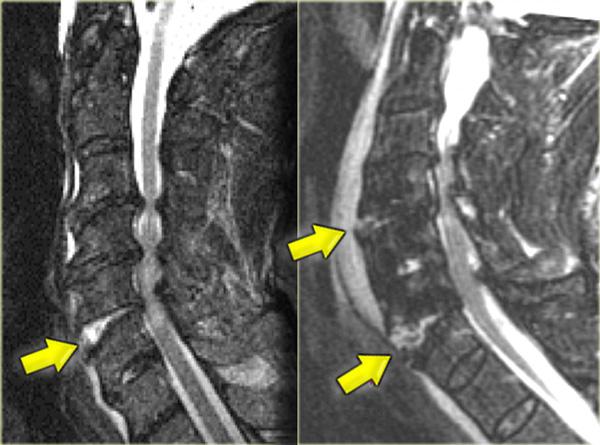

MRI giải thích tình trạng thần kinh của bệnh nhân này.

Các dấu hiệu trên MRI bao gồm:

- Tổn thương mô mềm nặng nề ở các cấu trúc cạnh sống phía sau, đặc biệt tại mức C5-6, nơi dây chằng gian gai và dây chằng vàng bị đứt

- Rách đĩa đệm C5-6 với di lệch ra phía sau C5

- Phù nề tủy sống lan rộng

Tiếp tục với hình ảnh mặt cắt axial.

Hình ảnh axial cho thấy tổn thương tủy sống và ngoài ra còn có sự vắng mặt của khoảng trống dòng chảy (flow void) ở động mạch đốt sống phải.

Điều này gợi ý huyết khối do bóc tách động mạch.

Kết luận, bệnh nhân này không có gãy xương, nhưng có bong gân tăng gấp nặng kèm thoát vị đĩa đệm cấp tính, tổn thương tủy sống không xuất huyết và huyết khối động mạch đốt sống.

Chụp mạch cộng hưởng từ (MRA) xác nhận tắc nghẽn động mạch đốt sống phải.